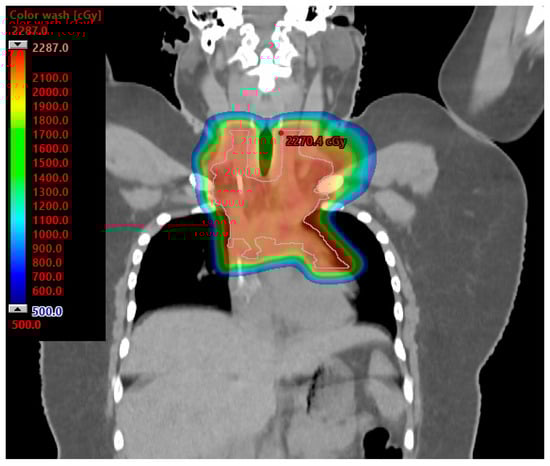

- MacDonald, S.M.; Jimenez, R.; Paetzold, P.; Adams, J.; Beatty, J.; DeLaney, T.F.; Kooy, H.; Taghian, A.G.; Lu, H.M. Proton radiotherapy for chest wall and regional lymphatic radiation; dose comparisons and treatment delivery. Radiat. Oncol. 2013, 8, 71. [Google Scholar] [CrossRef] [PubMed]

- Fagundes, M.; Hug, E.B.; Pankuch, M.; Fang, C.; McNeeley, S.; Mao, L.; Lavilla, M.; Schmidt, S.L.; Ward, C.; Cahlon, O.; et al. Proton Therapy for Local-regionally Advanced Breast Cancer Maximizes Cardiac Sparing. Int. J. Part. Ther. 2015, 1, 827–844. [Google Scholar] [CrossRef]

- Dabaja, B.S.; Hoppe, B.S.; Plastaras, J.P.; Newhauser, W.; Rosolova, K.; Flampouri, S.; Mohan, R.; Mikhaeel, N.G.; Kirova, Y.; Specht, L.; et al. Proton therapy for adults with mediastinal lymphomas: The International Lymphoma Radiation Oncology Group guidelines. Blood 2018, 132, 1635–1646. [Google Scholar] [CrossRef]